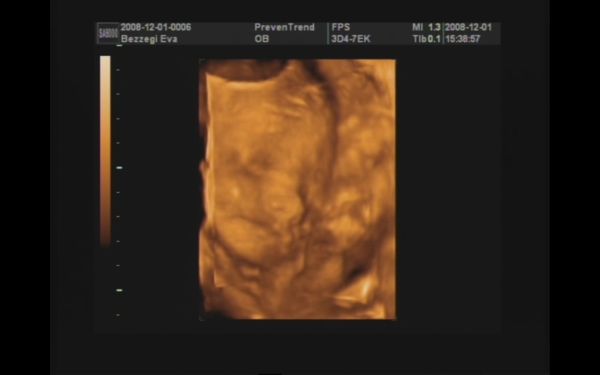

Majd jövök (ha a fiúktól egyszer visszaszerzem a gépet!!), addig is egy pár kép :D! 989 gramm a becsült súlya :shock: , két hete 776 gramm volt!!! Nagyon gyorsan gyarapszik ez a kis pöttömke! :D:D:D

Szerintem kommentálni nem kell :D!! Az integetős, mosolygós kép nekem nagyon tetszik!!